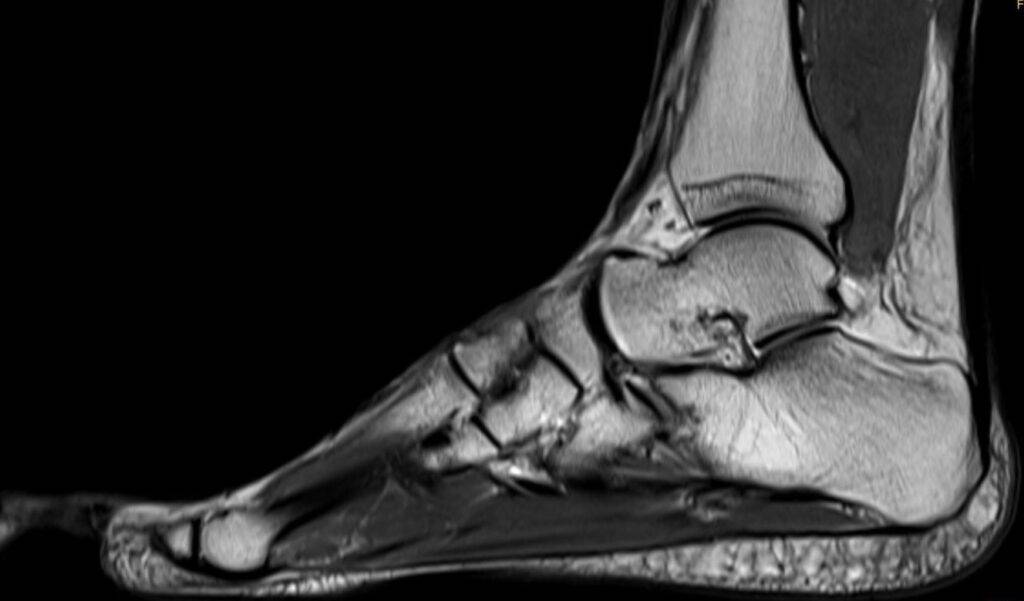

Fuß MRT Bild, verschiedene Perspektiven